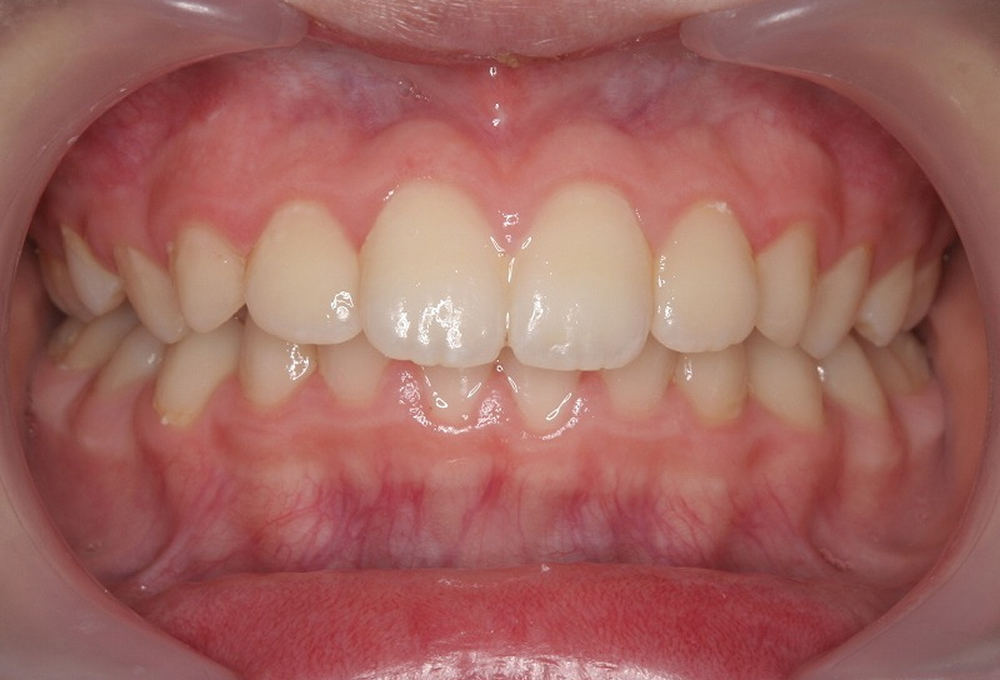

③術後